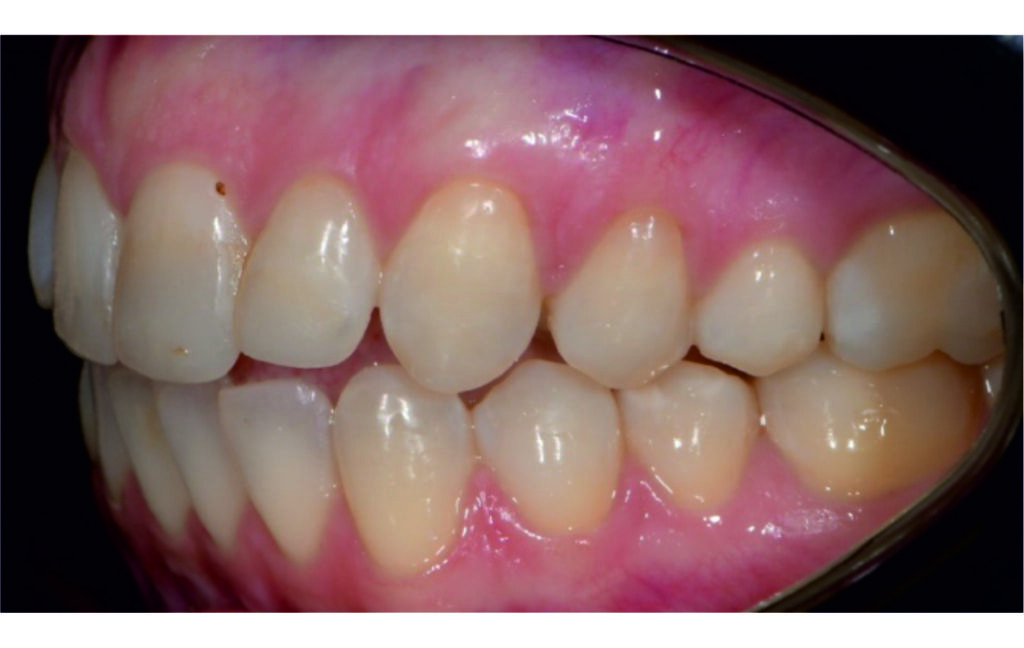

Angle Class II 2mm on the right, Angle Class II 2mm on the left, light mandibular asymmetry to the right, lower central line 1mm to the right, upper central line 1,5mm to the left, 1mm overjet and overbite. Sagittal asymmetry of upper dental arch. Light crowding upper and lower frontal segments, severe attrition of posterior teeth, night bruxism. Normal sagittal position of both jaws, high angle case, steep mandibular ramus,excessive lower facial height, open bite tendency.

The case initially presented as a moderate Class II on the right and a Class II tendency on the left, with tapered dental arches and an anterior open bite extending to tooth 26 in segment II.

A 1.5 mm deviation of the upper dental midline to the patient’s left was noted, along with a slight mandibular midline shift to the right, likely due to asymmetrical mandibular growth observed in the facial structure. Severe mesial rotations of teeth 16 and 26 were evident in the initial records. As derotation of 16, 26, 17, and 27 progressed up to aligner 16, the premolars in segments I and II moved distally, resulting in a bilateral Class I relationship, as intended in the initial treatment plan.